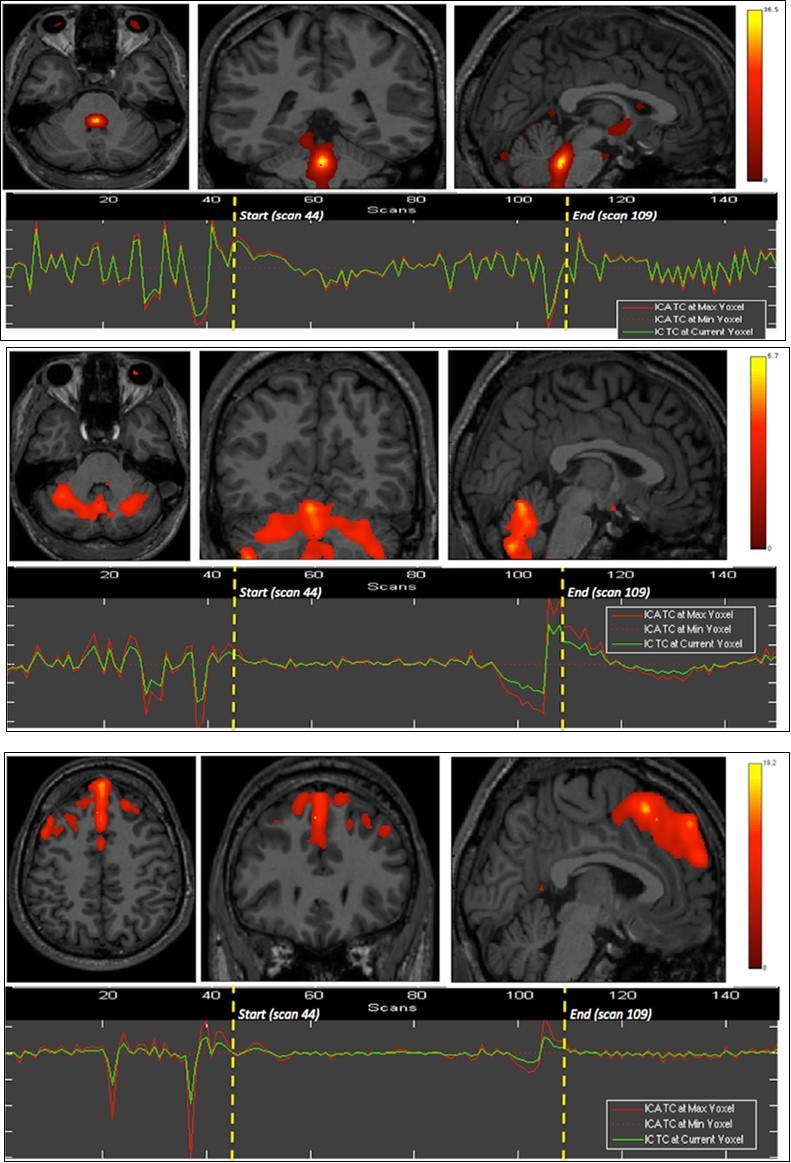

We found the dorsal pons, cerebellar hemispheres (superior aspect) and whole vermis, bilateral dorsal and ventromedial prefrontal, and medial occipital cortices to show significant BOLD signals differences as compared to the whole brain, during the first breath holding (Figure 1).

Figure 1.First experiment showing both BOLD signal time courses and activated areas: dorsal pons (1st row), anterior and posterior vermis as well as superior and lateral aspects of the cerebellar hemispheres (2nd row), dorsomedial prefrontal cortex (3rd row), and primary visual cortex (last row).

The apnea period was obviously recognizable on the time course of the BOLD signals graphs because of the striking change of the curves from breathing to apnea and after apnea, with very low fluctuations during apnea. Within eloquent brain areas TC curves showed various patterns: (i) high fluctuations mainly in the second half of apnea in the dorsal pons only (Figure 1-1st row), (ii) very low fluctuations with deep depression at the end of apnea in the cerebellum (Figure 1-2nd row) as well as in the supramarginal gyrus (Figure 2, lower row), less marked in occipital areas (figure 1-4th row), and (iii) flat curve in dorsomedial prefrontal (Figure 1-3), ventromedial prefrontal (Figure 2-upper row) and inferior parietal areas (Figure 2-middle row). The eloquent areas disclosed during both experiments are mapped on a brain mesh as nodes of both networks (Figure 3).